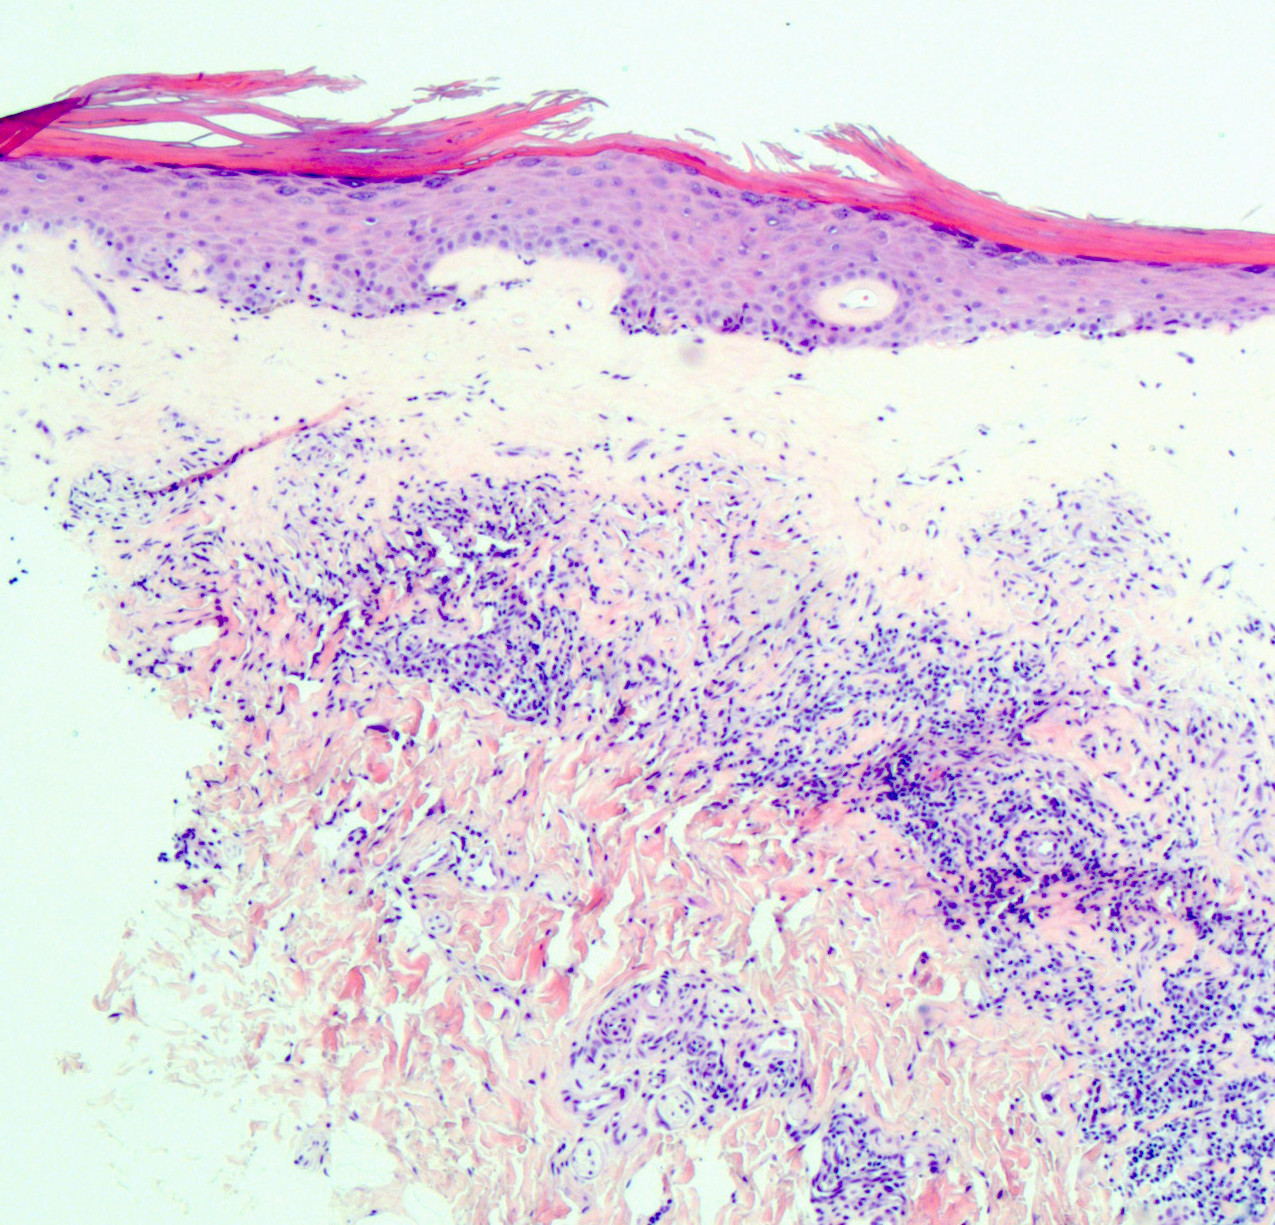

- Vacuolar interface reaction pattern in conjunction with dermal sclerosis (homogenized and hyalinized eosinophilic collagen bundles) of any thickness intervening between inflammatory infiltrate and epithelium or vessel walls (Mod Pathol 1998;11:844)

- Early lesions show only the inflammation and no or minimal fibrosis (inflammatory phase); the histopathological findings at this stage of disease development are not diagnostic

- Severe hyperkeratosis; thin epidermis, loss of rete pegs, basal cell degeneration, homogenized band of dense fibrosis at papillary dermis, upper dermal edema, band-like chronic inflammation

- In early stages, findings are subtle and often more prominent in adnexal structures than in interfollicular skin; adnexal structures show acanthosis, luminal hyperkeratosis and hypergranulosis

- Early dermal changes are homogenized collagen and wide ectatic capillaries in dermal papillae immediately beneath basement membrane

- Superficial dermal collagen may be wire-like with lymphocyte entrapment (J Cutan Pathol 2015;42:510)

- Lymphocytic infiltrate can be sparse or dense, lichenoid or interstitial with epidermal lymphocyte exocytosis

- Erosions or ulceration can occur (J Low Genit Tract Dis 2021;25:255)

Microscopic (histologic) images